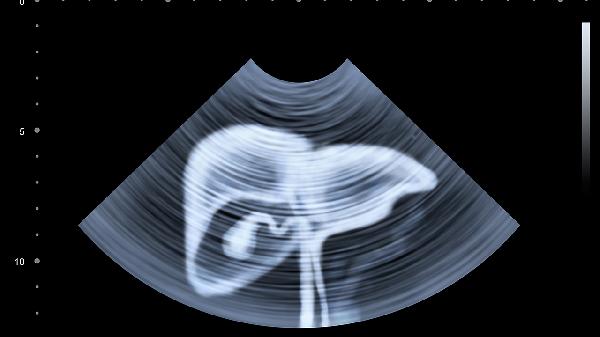

脾脏肿大或梗死可引起左季肋区持续性钝痛,常见于传染性单核细胞增多症、血液系统疾病。可能伴随发热、乏力等全身症状,触诊可发现脾脏增大。需通过血常规、腹部超声明确诊断。